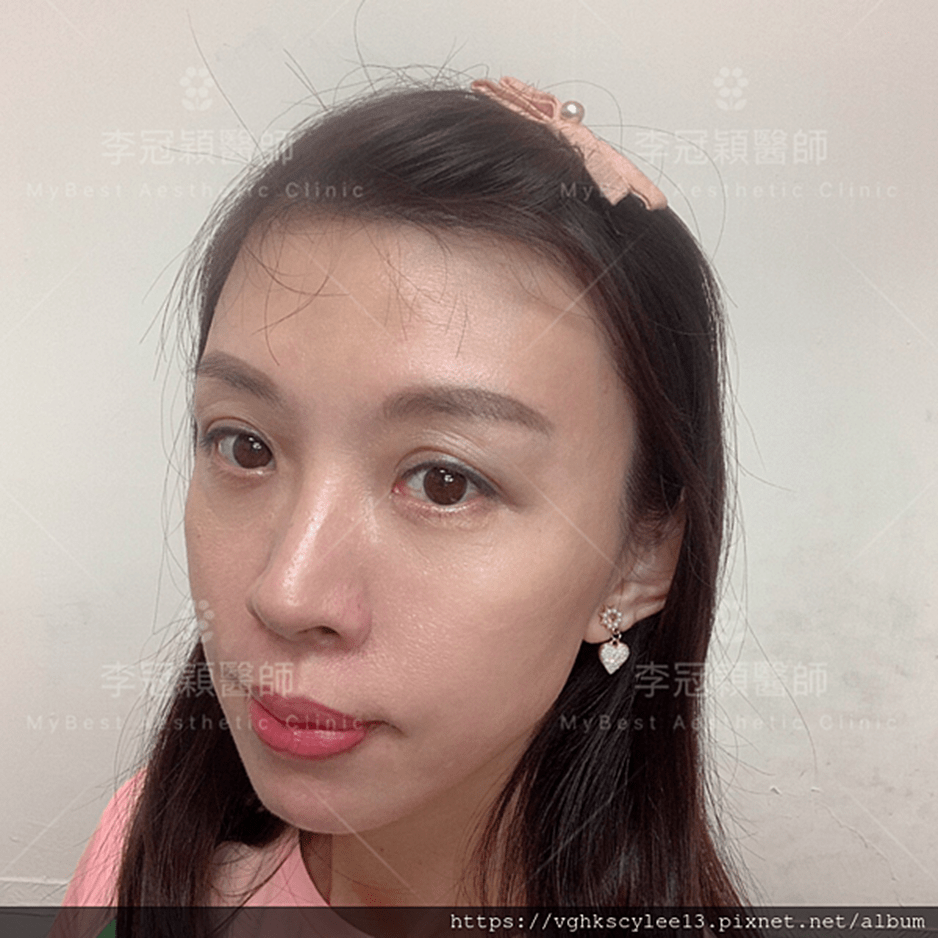

前 後(三個月)太陽穴到側額凹陷,眼尾下垂。(太陽穴不對稱往往來自顴骨大小不對稱)可以調整改善對稱性。

臉型不對稱 在太陽穴有一定落差,上圖經過太陽穴墊片矯正後,也明顯改善不對稱的視覺效果。重要的一點可以支撐眼尾下垂,改善老態眼神!(上圖)經內視鏡墊太陽穴跟提眼尾術後滿意。

(下圖)凹陷太陽穴,提前老態與眼尾下垂,經李醫師內視鏡太陽穴墊片支撐眼尾,幾乎不鬆垂完全抗老。

下圖:太陽穴墊片後兩年,眼尾支撐效果持久。